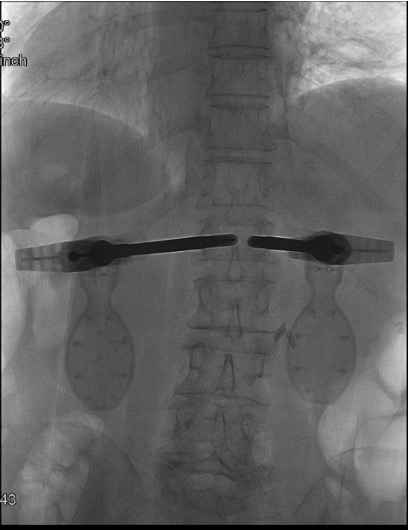

- Both implant expanders inserted through working cannulae, expanded simultaneously under fluoroscopy

Simultaneous mechanical expansion โ height restoration

Lock devices in expanded position

- Bilateral approach mandatory: SpineJack requires bilateral implant placement โ two cannulae, two devices, simultaneous expansion

Next step: Monitor both devices simultaneously on AP fluoroscopy during expansion. Slow the advancing device and apply more force on the lagging side to achieve symmetric height restoration. Small asymmetries are acceptable โ do not force symmetric expansion at the cost of superior end-plate breach.